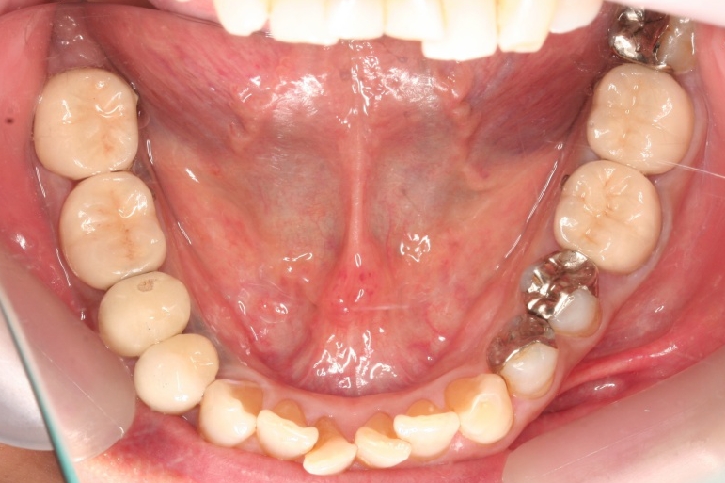

インプラント

担当歯科医師:佐藤英司

2013年5月3日千葉市若葉区 Y.T様 左下6番 インプラント上部構造